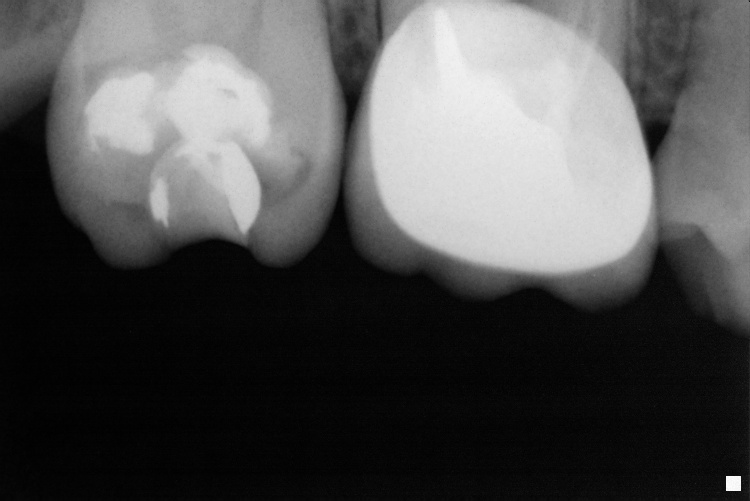

Name Last modified Size Description Parent Directory - IO000001.jpg 2020-07-28 13:55 84K IO000002.jpg 2020-07-28 13:55 68K IO000003.jpg 2020-07-28 13:55 83K IO000004.jpg 2020-07-28 13:55 92K